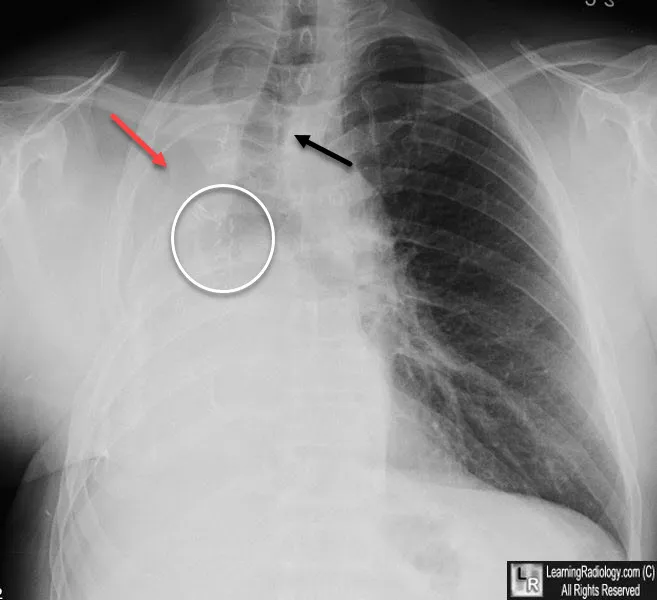

- Late (Months): Complete opacification. Marked mediastinal shift towards surgical side. Ipsilateral hemidiaphragm ↑. Contralateral lung hyperinflation. Ribs approximated.

Post-Pneumonectomy Syndrome (PPS)

- Late complication (months-years) due to extreme mediastinal shift/rotation causing airway (trachea/main bronchus) compression. More common post-right pneumonectomy.

- CT: Confirms airway compression between sternum/great vessels and vertebral column.